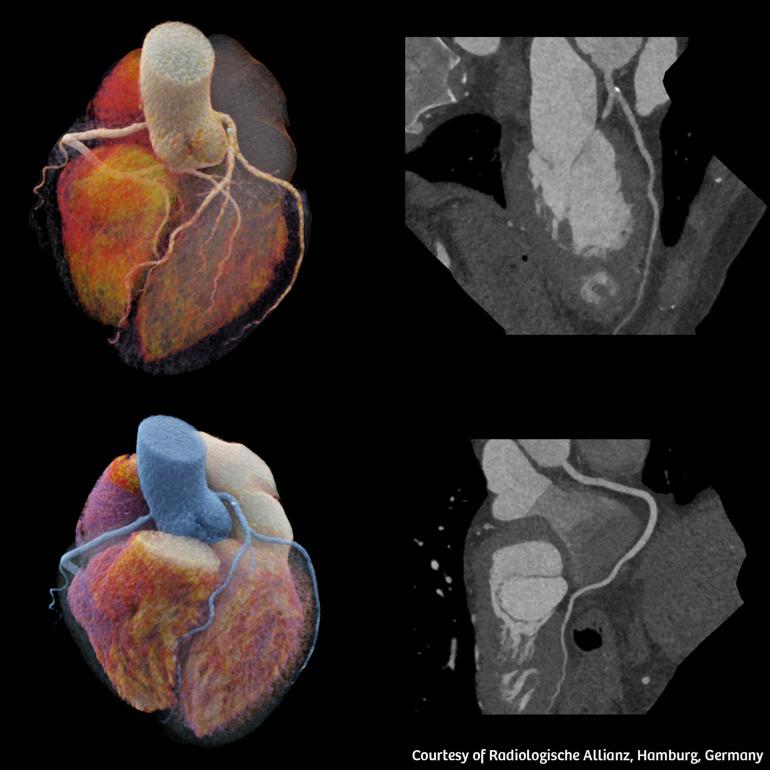

Η αξονική τομογραφία διπλής λυχνίας επιτρέπει την ιδιαίτερα υψηλή χρονική ανάλυση. Η υψηλή χρονική ανάλυση και η ταχύτητα σάρωσης αποτελούν σημαντικά στοιχεία στην αξονική τομογραφία καρδιάς, διότι περιορίζουν τα παράσιτα στην εικόνα λόγω της αναπνευστικής κίνησης ή της κίνησης της καρδιάς. Αυτό επιτρέπει τη σάρωση ασθενών με απαιτητικές κλινικές καταστάσεις, όπως ασθενείς που έχουν υψηλούς ή ακανόνιστους καρδιακούς παλμούς, αδυνατούν να συγκρατήσουν την αναπνοή τους ή αδυνατούν να μείνουν ακίνητοι, αλλά και ασθενείς που δυσκολεύονται να ακολουθήσουν τις οδηγίες του κλινικού ιατρού. Η χρήση φίλτρου κασσίτερου διατηρεί τη δόση ακτινοβολίας σε χαμηλά επίπεδα, διατηρώντας παράλληλα τη βέλτιστη ποιότητα εικόνας, ιδίως σε κλινικές ενδείξεις, όπως προληπτικού ελέγχου σαρώσεις θώρακα με εξαιρετικά χαμηλή δόση.

Στις δυνατότητες του SOMATOM Pro.Pulse αναφέρθηκε και ο Δρ. Quoc-Duy Vo, Διευθυντής του ακτινολογικού τμήματος στο Νοσοκομείο Morges στην Ελβετία2 και τόνισε: «Χαιρόμαστε που θα μπορέσουμε επιτέλους να χρησιμοποιήσουμε αυτή την υψηλή τεχνολογία στη μονάδα μας. Ο κλινικός ρόλος της αξονικής τομογραφίας επεκτείνεται, καθώς αναδεικνύεται σε βασικό παράγοντα για την έγκαιρη ανίχνευση και τον σχεδιασμό της θεραπείας. Γι’ αυτό το λόγο, χρειαζόμαστε ένα υψηλής απόδοσης σύστημα που να επιτρέπει τη διενέργεια εξετάσεων σε μία ακόμη πιο διευρυμένη ομάδα ασθενών. Με το SOMATOM Pro.Pulse μπορούμε να εκτελούμε υψηλής ποιότητας καρδιολογικές απεικονίσεις, καθώς και ιατρικές απεικονίσεις σε άλλους τομείς της ακτινολογίας».